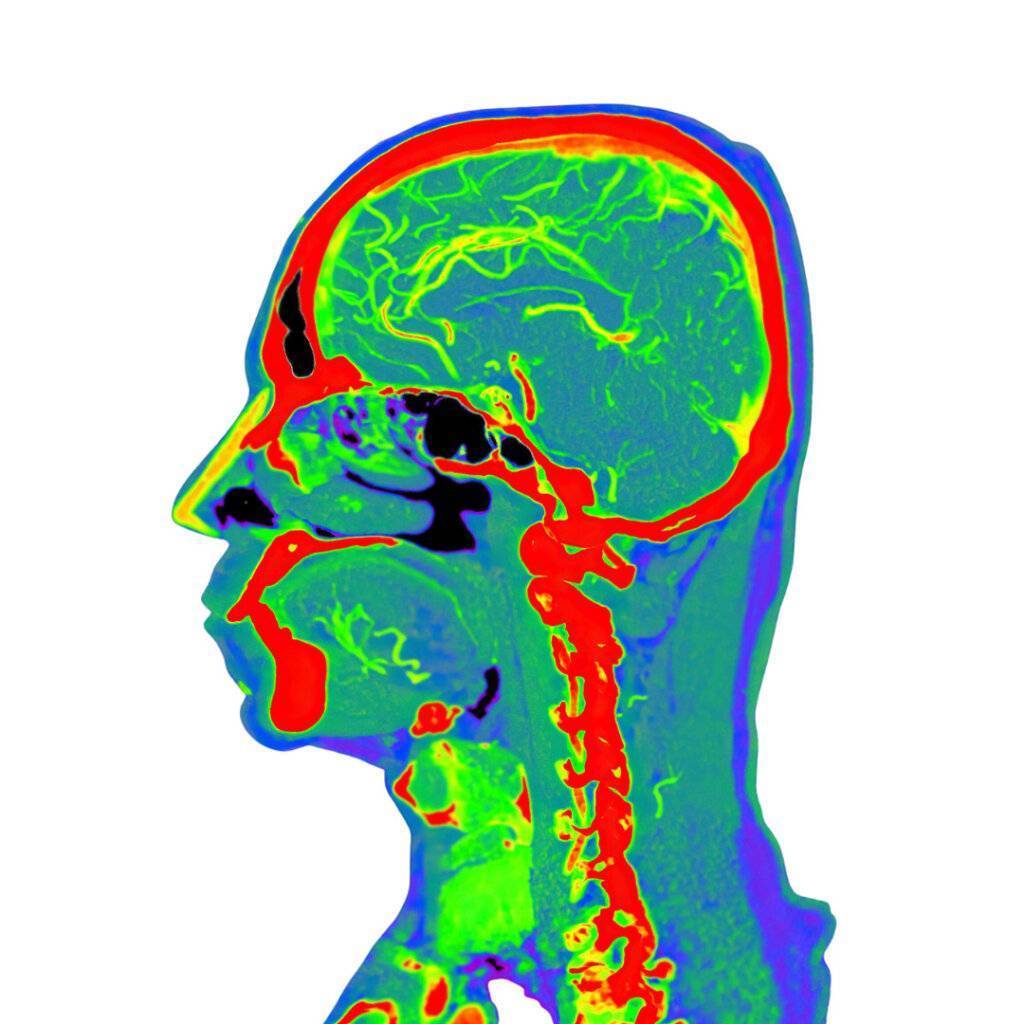

CT Kopf ist eine nicht-invasive Bildgebungstechnik, die Röntgenstrahlen verwendet, um detaillierte Bilder des Kopfes zu erstellen und wichtige Informationen für die Diagnose und Behandlung verschiedener Erkrankungen des Gehirns und der umgebenden Strukturen zu liefern.

Die Computertomographie, allgemein bekannt als CT oder CAT (Computertomographie), hat die medizinische Bildgebung revolutioniert, insbesondere wenn es um die Untersuchung des Kopfes und des Gehirns geht.

Eine CT-Kopfuntersuchung kann eine Vielzahl wichtiger Informationen liefern, einschließlich:

- Traumata und Frakturen: Die CT kann Frakturen erkennen und den Umfang von Kopfverletzungen nach Traumata beurteilen.

- Blutungen und Hämatome: Sie ist äußerst effektiv bei der Identifizierung akuter Blutungen im Gehirn.

- Tumoren und Läsionen: Die CT hilft bei der Lokalisierung und Charakterisierung von Hirntumoren und Läsionen.

- Vaskuläre Anomalien: Sie kann vaskuläre Anomalien wie Aneurysmen oder arteriovenöse Malformationen visualisieren.

- Infektionen und Entzündungen: Die CT kann das Vorhandensein von Infektionen oder Entzündungen im Gehirn anzeigen.

In bestimmten Fällen können Kontrastmittel bei einer CT-Kopfuntersuchung verwendet werden. Diese Kontrastmittel verbessern die Sichtbarkeit von Blutgefäßen und bestimmten Geweben, was zur Diagnose bestimmter Zustände wie vaskulärer Anomalien oder Tumoren beiträgt.